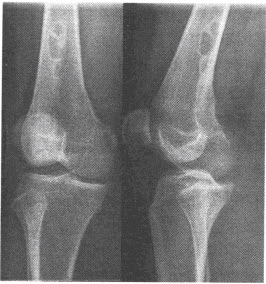

D.����ЧӦ

�У�20�꣬��С���϶���ʹ2�����ࡣ�����ϥ�ؽ�����λƬ������ܵ����Ϊ����